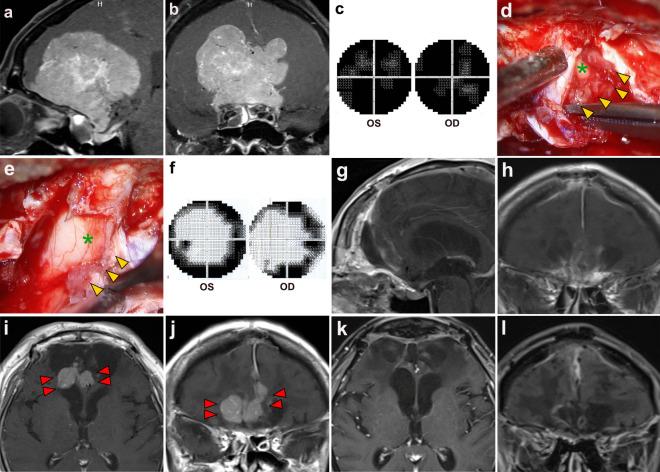

There is a lack of available data regarding the incidence and characteristics of optic canal invasion (OCI) in large midline non-tuberculum sellae anterior skull base meningiomas (NTSAM), specifically those originating predominantly from the olfactory groove and planum sphenoidale. This study aims to describe the incidence and characteristics of OCI as well as clinical and visual outcomes following extensive tumor resection with optic canal exploration in intra-optic canal tumor removal. In addition, the predictive performance of OCI by preoperative magnetic resonance imaging (MRI) is investigated.

MATERIALS AND METHODS

From 2016 to 2024, we retrospectively reviewed 24 patients with large midline NTSAM who underwent extensive tumor resection in our institution. The OCI was evaluated and compared between preoperative MRI and intraoperative findings. The OCI was classified as follows. Type 1 represented no invasion, type 2 represented secondary invasion, type 3 represented partial wall invasion (two subtypes), and type 4 represented invasion into the superior-medial-inferior walls of the optic canal. Visual functions were assessed before and after surgery.

RESULTS

Among 24 patients, a mean tumor size of 57.2 mm (range 39.0-79.0). The OCI was observed intraoperatively in 22 cases (91.7%), with 19 cases exhibiting bilateral OCI. Among the 48 optic canals in the 24 patients, 18 (37.5%) were type 4, 12 (25.0%) were type 3-inferomedial, 9 (18.8%) were type 3-superomedial, and 2 (4.2%) were type 2, where 7 (14.6%) optic canals were without OCI. A significant correlation was observed between intraoperative OCI and the tumors that exhibited involvement of the tuberculum sellae (TS) on MRI (p < 0.001). For patients with visual impairment, the vision in 27 of 38 (71.1%) eye sides showed improvement following the surgery. There was 1 (4.2%) case of tumor recurrence at the mean follow-up time of 27.3 months (range 4-73 months).

CONCLUSIONS

A high incidence of OCI was observed in the large midline NTSAM. The identification of TS involvement on MRI can serve as a strong predictor of OCI. Therefore, optic canal exploration to remove the optic canal invasion during the surgical removal of these particular tumors should be contemplated to attain radical tumor resection to enhance the possibility of improving visual function and reduce the risk of recurrence.

关于大型中线非蝶骨嵴鞍结节前颅底脑膜瘤(NTSAM),特别是主要起源于嗅沟和蝶骨平台的脑膜瘤,视神经管侵犯(OCI)的发生率和特征的可用数据匮乏。本研究旨在描述OCI的发生率和特征,以及在视神经管内肿瘤切除术中进行广泛肿瘤切除并探查视神经管后的临床和视觉结果。此外,还研究了术前磁共振成像(MRI)对OCI的预测性能。

材料与方法

2016年至2024年,我们回顾性分析了在我院接受广泛肿瘤切除的24例大型中线NTSAM患者。对视神经管侵犯情况在术前MRI和术中发现之间进行评估和比较。OCI分类如下。1型表示无侵犯,2型表示继发性侵犯,3型表示部分壁侵犯(两个亚型),4型表示侵犯视神经管的上、中、下壁。在手术前后评估视觉功能。

结果

24例患者中,肿瘤平均大小为57.2mm(范围39.0 - 79.0mm)。术中观察到22例(91.7%)存在OCI,其中19例为双侧OCI。在24例患者的48条视神经管中,18条(37.5%)为4型,12条(25.0%)为3型 - 下内侧型,9条(18.8%)为3型 - 上内侧型,2条(4.2%)为2型,7条(14.6%)视神经管无OCI。术中OCI与MRI显示累及蝶骨嵴(TS)的肿瘤之间存在显著相关性(p < 0.001)。对于有视力障碍的患者,38只患眼中有27只(71.1%)术后视力改善。在平均随访时间27.3个月(范围4 - 73个月)时,有1例(4.2%)肿瘤复发。

结论

在大型中线NTSAM中观察到OCI的高发生率。MRI上TS受累的识别可作为OCI的有力预测指标。因此,在手术切除这些特定肿瘤时,应考虑探查视神经管以去除视神经管侵犯,以实现肿瘤的根治性切除,提高改善视觉功能的可能性并降低复发风险。